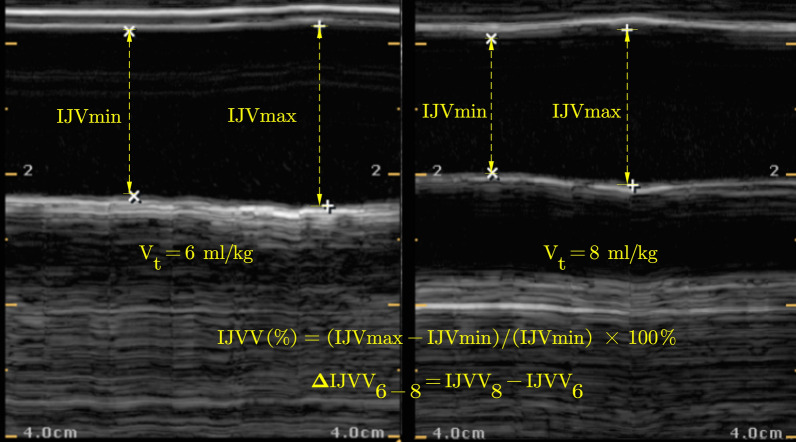

Methods: This was a prospective study conducted in the operating room. Patients were studied at baseline (a Vt of 6 ml kg-1 PBW), during a 1 min increase in the Vt to 8 ml kg-1 of the PBW, during a 1 min shift to the Trendelenburg maneuver, and after fluid administration. Baseline values of the IJVV, pulse pressure variation (PPV), and stroke volume variation (SVV) [IJVV6, PPV6, and SVV6, respectively], and the changes in the IJVV during a TVC (ΔIJVV6-8) were measured. The change in cardiac index during a Trendelenburg maneuver (ΔCItrend) was also recorded. Volume responsiveness was defined by a ΔCItrend ≥ 8%. The primary outcome was determination of the ΔIJVV6-8 in predicting volume responsiveness during low Vt ventilation in the prone position. The secondary outcomes included an estimation of the IJVV6, PPV6, and SVV6 diagnostic performances in predicting volume responsiveness in this surgical setting.